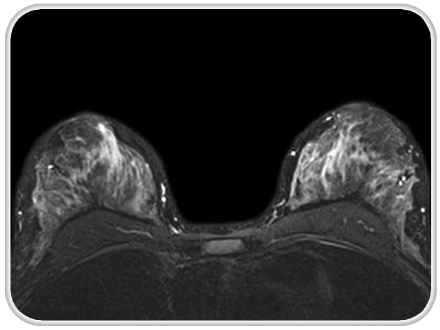

در بررسیهای جدید مشخص شده است که استفاده از تصویربرداری رزونانس مغناطیسی (MRI) بهمنظور بررسی اثر شیمیدرمانی بر سرطان پستان بسیار دقیقتر از ارزیابیهای بالینی است، که این امر برای شیمیدرمانی قبل از جراحی بسیار کمککننده است.

این تحقیق که توسط گروه رادیولوژی دانشگاه کالیفرنیا انجام شده نشان داد که استفاده از شیمیدرمانی قبل از جراحی سبب کوچک شدن توده میشود و از طریق MRI میتوان به دقت مشخص کرد که آیا بیماران به شیمیدرمانی سرطان پستان پاسخ میدهند یا خیر.

این بررسی نشان داد که تغییر حجم تومور بعد از دوره اول درمان راهنمای بسیار خوبی است و نشان میدهد که بیمار به شیمیدرمانی پاسخ مناسب داده است یا خیر.